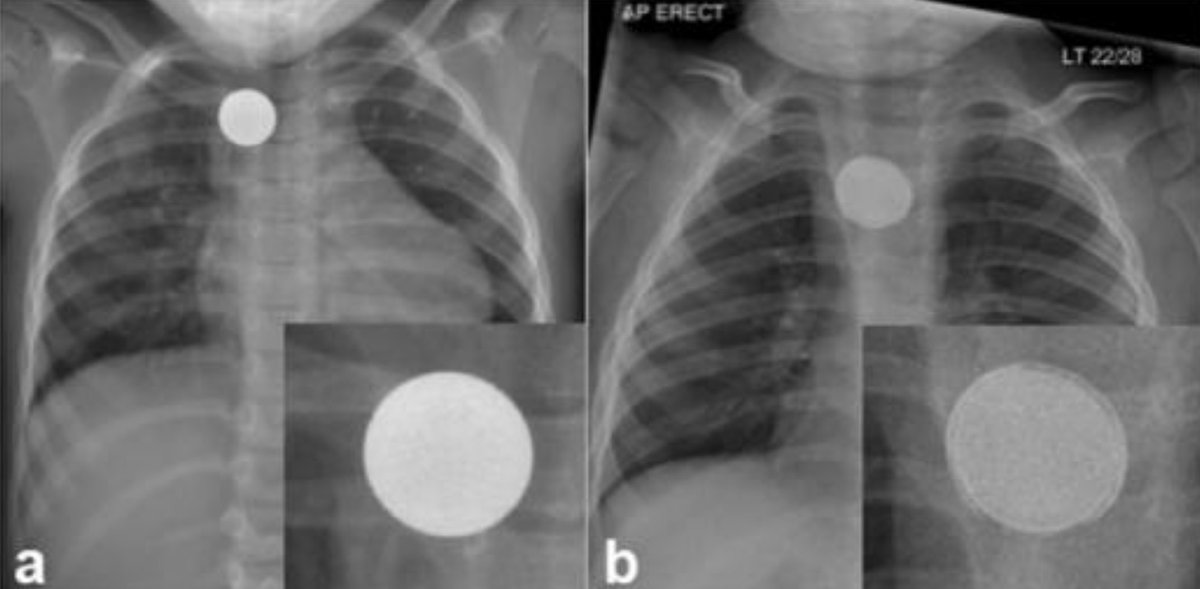

Votre réflexe en voyant ça?

Une simple pièce de monnaie?

Ou bien une pile bouton qui peut brûler les parois de l'oesophage puis de l'aorte et entrainer des vomissements de sang et un décès brutal?

Les piles boutons, ce danger insoupçonné pour les enfants, partout chez vous: Comment ça arrive ? Les piles boutons sont partout: dans les télécommandes, les jouets pour enfant, les livres musicaux.. Généralement sécurisées par des trappes ou des vis, mais un instant d'inattention et un enfant peut tout à fait l'avaler même sous la surveillance des parents